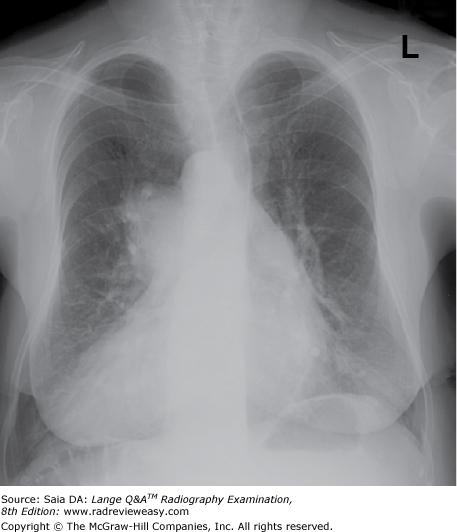

Which of the following statements is (are) true regarding the radiograph shown in Figure 6–16?

- The part is rotated.

- The patient is not shielded correctly.

- There is excessive receptor exposure.

A 1 only

B 2 only

C 1 and 2 only

D 1, 2, and 3

-The patient is well positioned; the spinous processes and sternum are seen clearly without superimposition. Adequate penetration and long-scale contrast are present without excessive receptor exposure. The patient had been shielded properly for the PA projection, but the shield was not moved to the correct location prior to the lateral exposure.